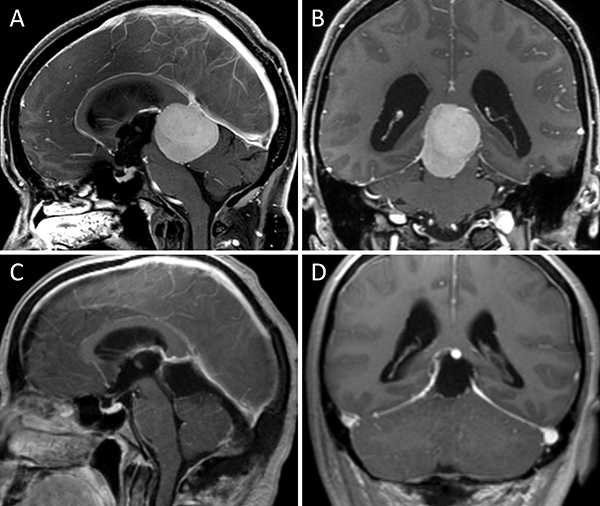

Figura 1. Meningioma tentorial medial. A-B: RM preoperatoria; C-D: RM postoperatoria.